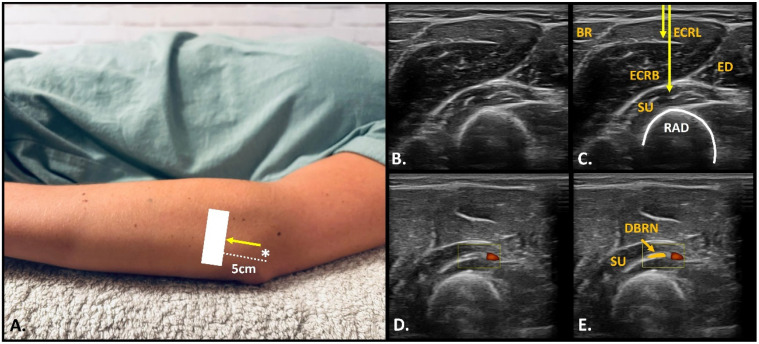

Abstract Image